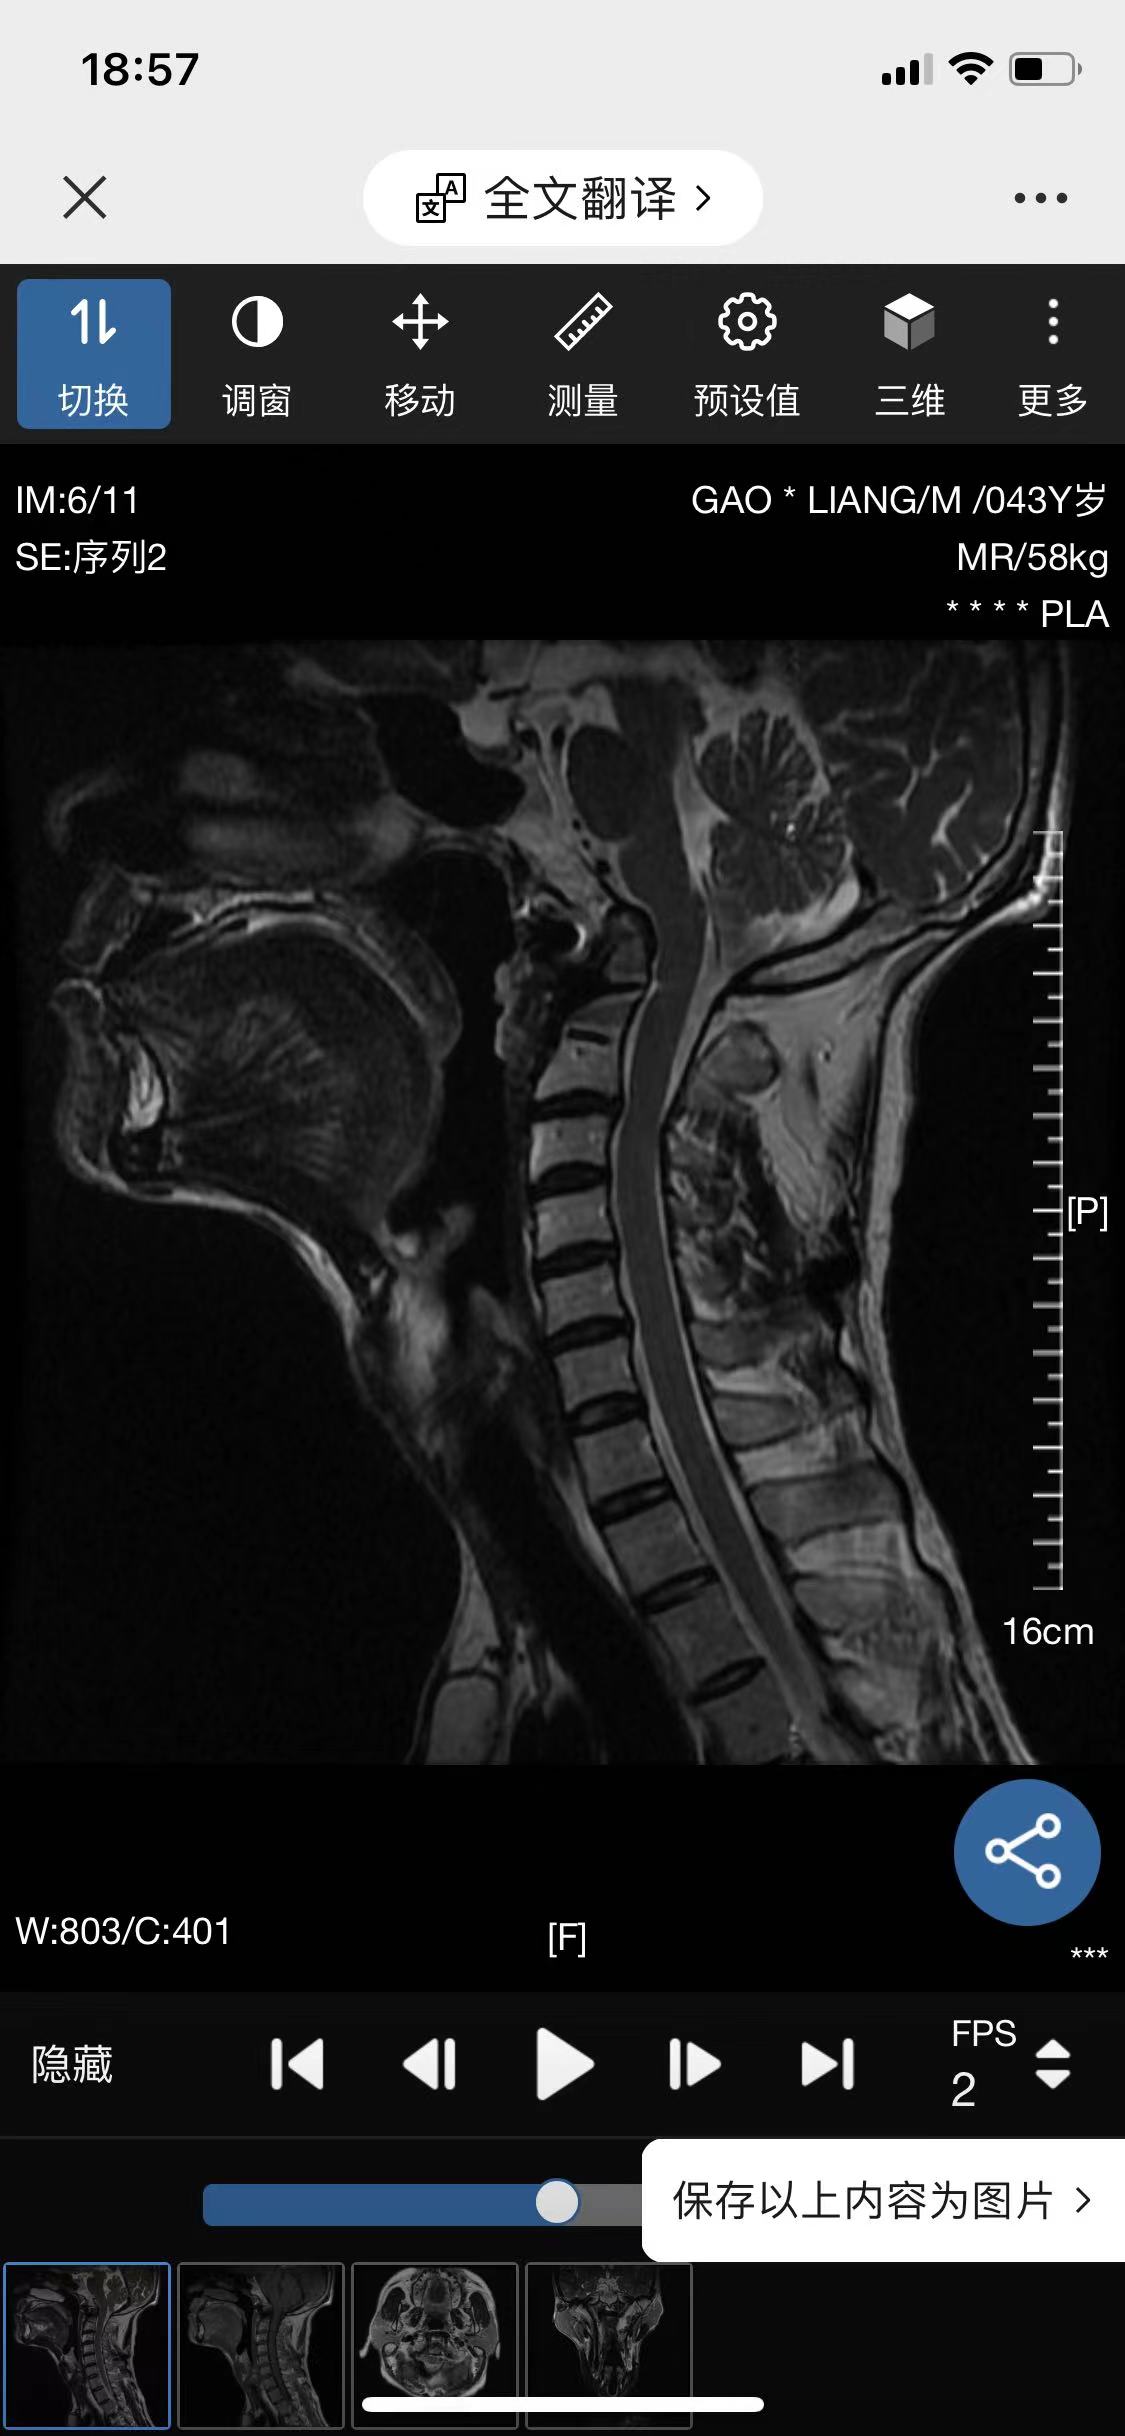

• 诊断:寰枢椎脱位

• 影像: